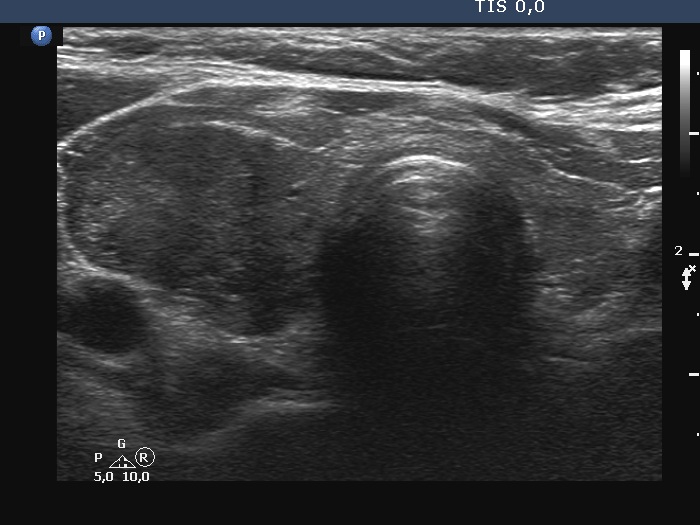

Ultrasonography. The right lobe was substantially enlarged and hypoechoic. It had macrocalcifications. The issue was whether the lobe was composed of a large nodule or only diffuse enlargement was present. The left lobe was much smaller. This lobe was also hypoechoic but to a lesser extent as was the right lobe. The vascularity was increased in the right while decreased in the left lobe.

The issue was whether the lobe was composed of a large nodule or only diffuse enlargement was present. On some still images, it seemed evident that there was a nodule. But we should never forget, that the reality is much more represented by videos. When we stop the continuous scan significantly affects what we see in a still image, which can therefore very easily be misleading. In the video, I highlighted those features on which we could decide considering only the ultrasound presentation that this very likely a nodule.